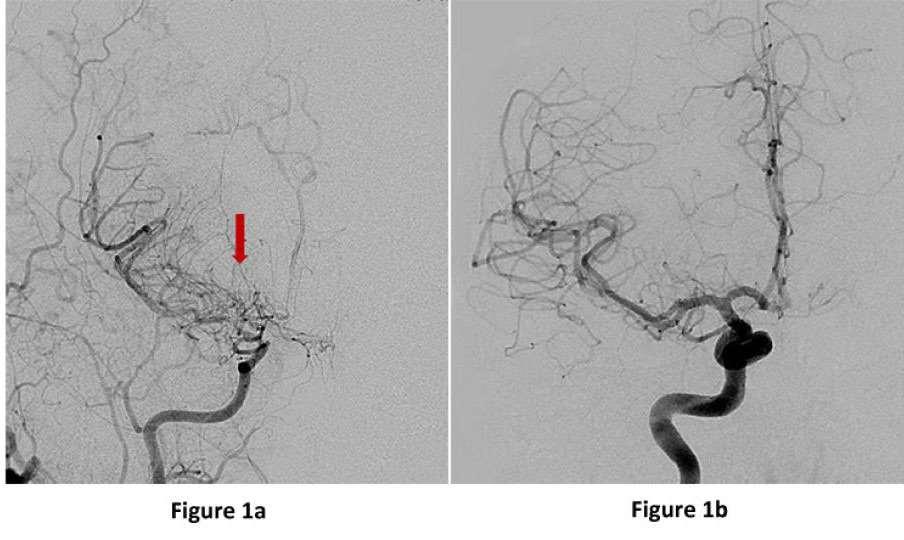

Figura1a:vistafrontaldeunaangiografíacerebralque muestraelestrechamientodelaarteriacarótidainterna derechaenlospequeñosovillosdevasosMoyamoya "bocanadadehumo"(flecharoja).Figura1b:Un angiogramanormalparacomparación(BaylorMedicine, Healthcare:Neurosurgery,2023).